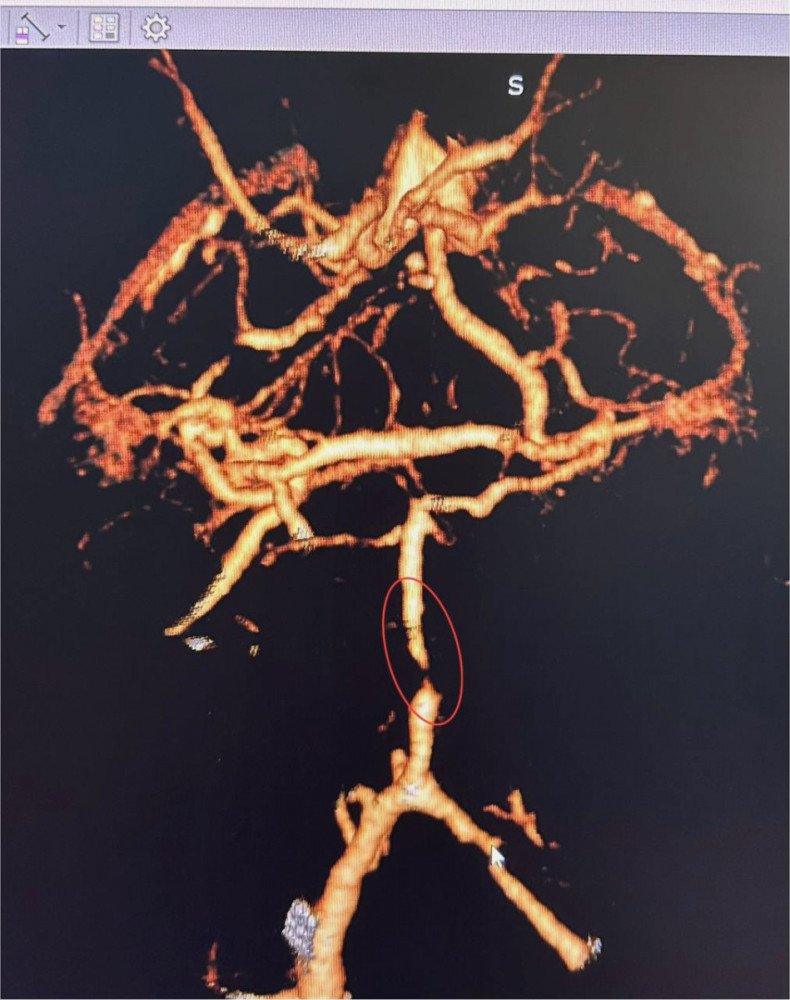

Завідувач рентгенендоваскулярного відділення Олександр Скрипка повідомив, що це був один з найскладніших випадків - ураження стовбура мозку. Базилярна артерія була практично повністю заблокована атеросклерозом. Такі інсульти є надзвичайно небезпечними, а без термінового втручання шанси на виживання практично зникають.

Лікарі вирішили провести операцію з ангіопластики артерії. Лікарня №10 має досвід у цій методиці для лікування коронарних артерій, але її використання для артерій мозку є новаторським підходом в Україні.

Операція тривала близько години. Звужену артерію розширили за допомогою спеціального балона, а потім використали балон з лікарським покриттям.